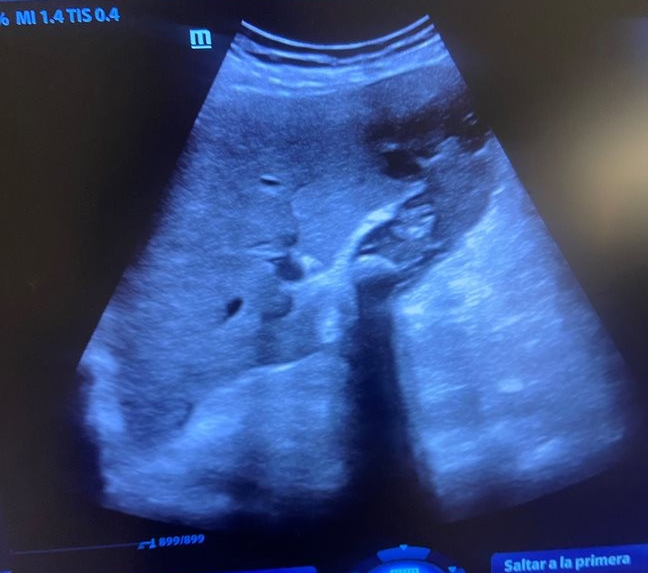

Paciente 4: en ovario derecho imagen anecoica con septos y tabiques con contenido en su interior se deriva a ginecólogo preferente ante sospecha de quiste complicado.

Paciente 5: asa intestinal incarcerada no reductible, se remite a urgencias donde es intervenida.